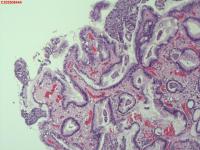

胃体粘膜

一般病史

腹部不适

标本名称

大体所见

胃体可见多发直径2mm息肉,稍隆起,圆丘形

增生性息肉

符合增生性息肉。

固有层粉染的是免疫球蛋白吗?